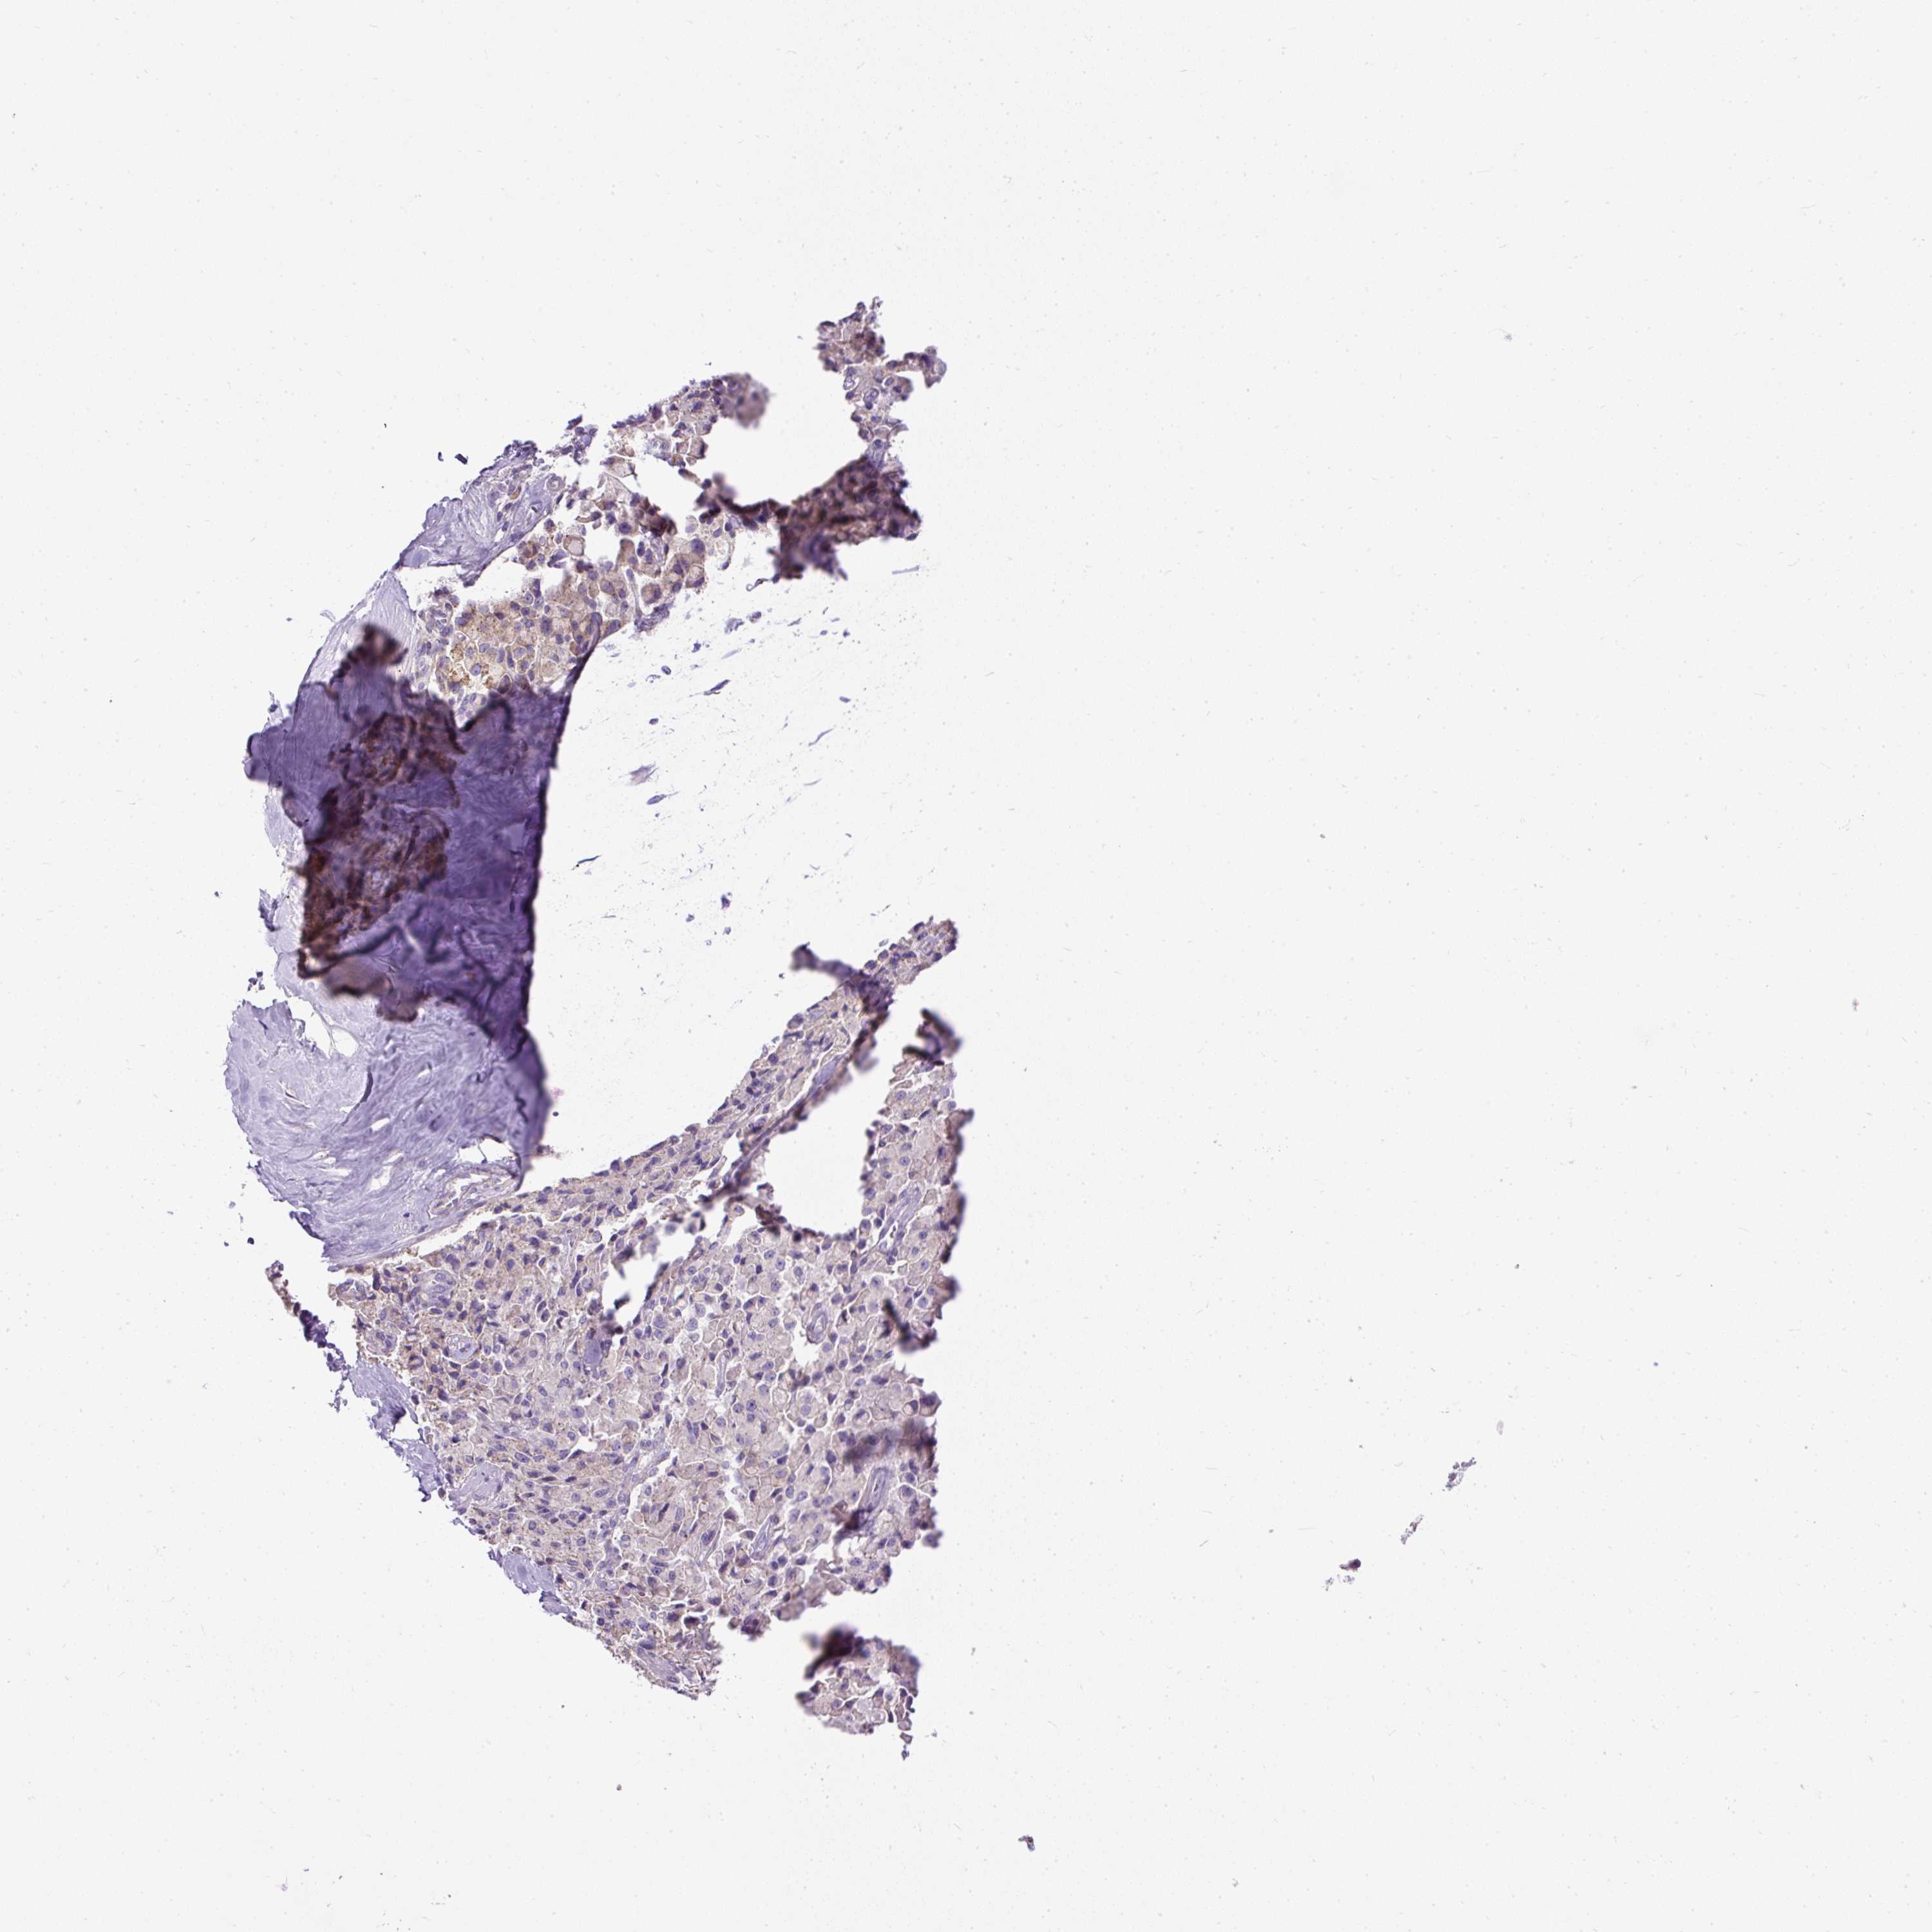

PANCREATIC CANCER - Protein expressioni

A mouse-over function shows sample information and annotation data. Click on an image to view it in a full screen mode. Samples can be filtered based on level of antibody staining by selecting one or several of the following categories: high, medium, low and not detected. The assay and annotation is described here.

Note that samples used for immunohistochemistry by the Human Protein Atlas do not correspond to samples in the TCGA dataset.

Antibody stainingi

Antibody staining in the annotated cell types in the current human tissue is reported as not detected, low, medium, or high, based on conventional immunohistochemistry profiling in selected tissues. This score is based on the combination of the staining intensity and fraction of stained cells.

Each image is clickable and will lead to virtual microscopy that enables deeper exploration of all samples and also displays staining intensity scores, fraction scores and subcellular localization as well as patient and tissue information for each sample.

Antibody HPA044633

Antibody HPA054859

Staining

High

Medium

Low

Not detected

Intensity

Strong

Moderate

Weak

Negative

Quantity

>75%

75%-25%

<25%

None

Location

Nuclear

Cytoplasmic/membranous

Cytoplasmic/membranous,nuclear

Adenocarcinoma, NOS